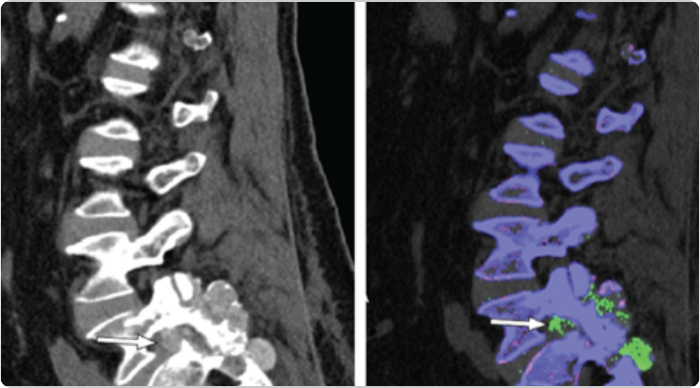

DECT scans of lower spine showing tophaceous deposits

Sagittal DECT and 3-dimensional DECT reconstruction show extensive tophaceous deposits (in green) in L1/2, L2/3, L3/4, and L4/5 lumbar discs, and also L2-L3 and L4-L5 facet joints.2

Adapted from Lu H, et al. Medicine (Baltimore). 2017;96:e7670.

KRYSTEXXA has not been studied to reverse damage to the spine or any of the body's organ.

DECT, dual-energy computed tomography.

DECT scans of lumbar spine showing tophaceous deposits

Sagittal mixed 120-kVp equivalent images of lumbar spine obtained with dual-energy CT demonstrate an intermediate-attenuation mass in the L5-S1 facet joint with bony erosions and narrowing of the neural foramen (arrow, left). Dual-energy material labeling color map overlay shows monosodium urate (green) and bone (blue and pink). Note the monosodium urate crystals crowding the left neural foramen (arrow, right).3

Adapted from Gibney B, et al. Radiology. 2020;296:276.

CT, computed tomography.